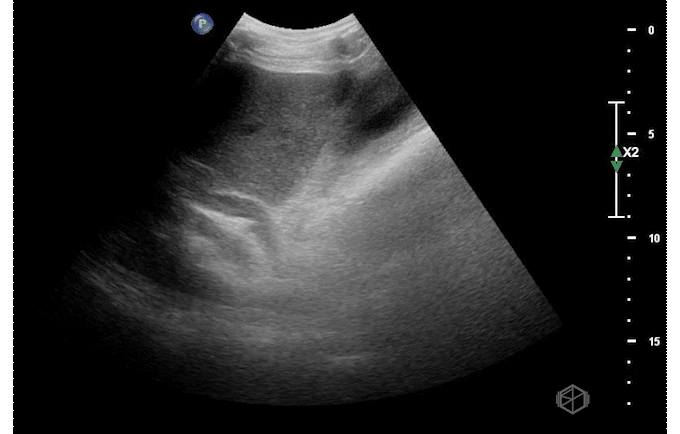

Ultrasound of the right upper quadrant demonstrated the below:

This ultrasound demonstrates a dilated common bile duct with mild gallbladder wall thickening.

• Finding the common bile duct is often difficult for novice sonographers. The common bile duct lies on top of the portal vein in long orientation making a “double barrel” type configuration as seen above. Color doppler may be used to determine the duct as there should be no flow. This is often easier to identify than the “Mickey Mouse” in short orientation.

• Due to the difficulty in determining the difference between the common hepatic duct and the common bile duct, some prefer to just call this structure the common duct (504652).

• If the labs are normal and there is no gallbladder wall thickening, pericholecystic fluid, or sonographic Murphy’s — there is little utility in finding the CBD (29162442).

• The CBD is measured inner to inner. There are various average sizes and no standard cut off but a common rule of thumb is that a dilated common bile duct is considered >4mm, increasing by 1 every decade at 50 and after. So a 70-year-old can have up to a 7mm sized CBD (14510259).

• Later studies have questioned this, however it is still considered a rule of thumb (28668951). In general, the CBD should remain under 6-7mm which is commonly accepted range for normal (11065260).